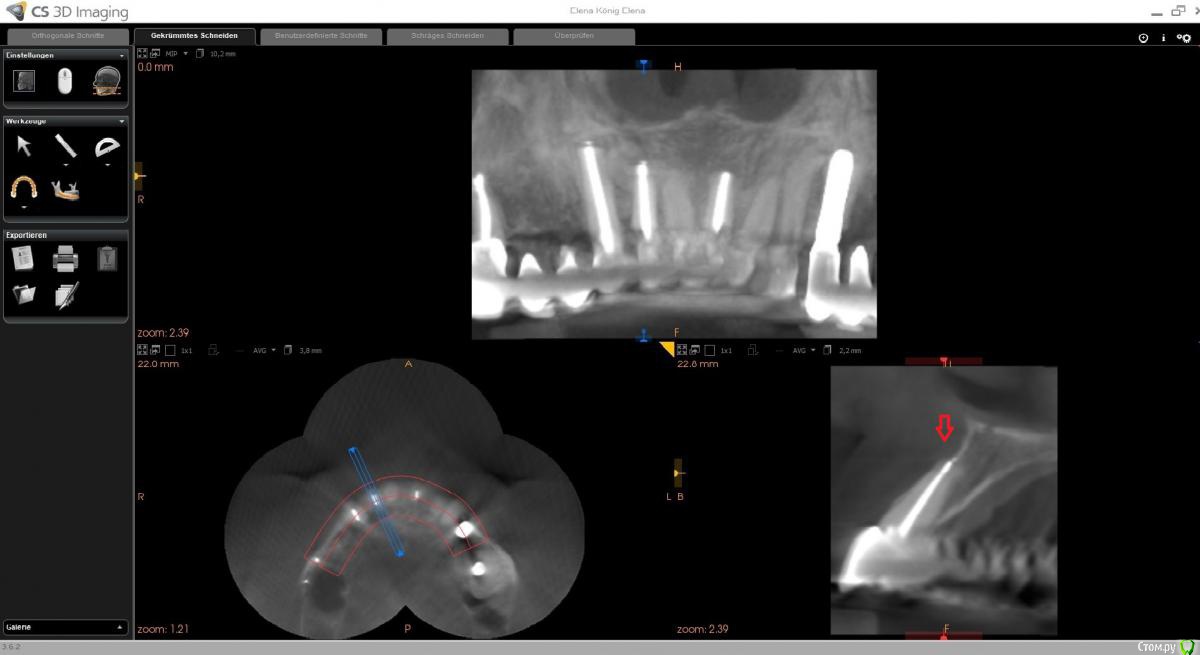

wladdX Опубликовано 10 февраля, 2020 Поделиться Опубликовано 10 февраля, 2020 (изменено) Вот ещё пара скриншотов. Очень непривычная для меня программа, так толком и не разобрался. Изменено 10 февраля, 2020 пользователем wladdX Ссылка на комментарий

wladdX Опубликовано 12 февраля, 2020 Поделиться Опубликовано 12 февраля, 2020 (изменено) Кстати, вот то, о чём говорил Bier, возможно, в этом причина. Изменено 12 февраля, 2020 пользователем wladdX Ссылка на комментарий